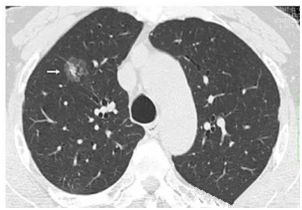

肺部小結(jié)節(jié)通常是指影像檢查(X線或者CT)中發(fā)現(xiàn)的直徑≤2cm的類圓形病灶,≤3cm的稱為結(jié)節(jié),>3cm的稱為腫塊。

也有學(xué)者認(rèn)為,分得太細(xì)并無(wú)意義,例如2.2cm的結(jié)節(jié)與1.9cm的小結(jié)節(jié),臨床上并沒(méi)有本質(zhì)的區(qū)別。在這里我們統(tǒng)一把≤3cm的結(jié)節(jié)統(tǒng)稱為肺部小結(jié)節(jié),在肺部小結(jié)節(jié)中,60%—70%為良性結(jié)節(jié),30%—40%的結(jié)節(jié)方為惡性結(jié)節(jié),所以,發(fā)現(xiàn)肺部小結(jié)節(jié)切勿驚慌。

結(jié)節(jié)的大、小與良、惡性有一定的相關(guān)性,當(dāng)肺部結(jié)節(jié)>3cm的病灶多為惡性,而微小的結(jié)節(jié),良性的可能性居多。

我們常看到的影像學(xué)描述中的“磨玻璃結(jié)節(jié)(GGO)”,其中一部分是非典型腺瘤樣增生(AAH)或原位腺癌(AIS),結(jié)節(jié)內(nèi)部的實(shí)變與生長(zhǎng)速度的加快(范圍變大)常意味病變性質(zhì)的轉(zhuǎn)變,可以逐步演變?yōu)槲⒔?rùn)腺癌(MIS)、浸潤(rùn)性腺癌(IAC)。